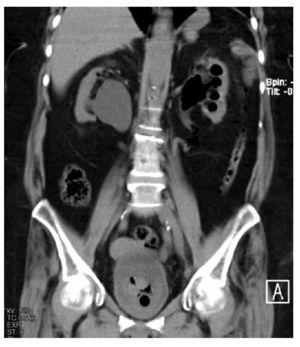

El caso que presentamos es una paciente con infección de vías urinarias complicada en pielonefritis enfisematosa bilateral, secundaria a uropatía obstructiva por la vena ovárica bilateral, por lo anterior tiene la particularidad de estar en el 11% de la presentación general, ya que dentro de los estudios de imagen no se evidenció la presencia de otro proceso obstructivo que condicionara la ureteropielocaliectasia y por consiguiente, el proceso enfisematoso. El cuadro clínico fue muy inespecífico, y la paciente fue ingresada por complicación de una pielonefritis enfisematosa. En la Figura 1, se observa un proceso enfisematoso en el uréter en el tercio proximal derecho. En la Figura 2, se observa ectasia bilateral con gas en parénquima renal en el polo superior derecho y en las cavidades del riñón izquierdo, así como el uréter del mismo lado, también se alcanza a observar la presencia de una escotadura en el uréter superior izquierdo y algo del derecho, justo por debajo de la unión ureteropiélica, que es el lugar donde se cruza con la vena ovárica.

En la Figura 3 se observa como la vena ovárica izquierda ingresa a la vena renal ipsilateral, produciendo ectasia ureteral desde el cruce de las ilíacas, se demuestra que es el sitio donde se cruza el uréter y la vena ovárica, allí se manifiesta la escotadura antes mencionadas, también demostrándose en esta figura la ectasia derecha con gas parenquimatoso hacia el polo superior. En la Figura 4 resalta del lado derecho, justo donde se cruza la vena ovárica con el uréter es donde se produce la ectasia a nivel de la bifurcación de la aorta en ilíacas primitivas, y del lado izquierdo en el cruce ureteral con los vasos ilíacos nuevamente se cruza con la vena ovárica produciendo ectasia.

Figura 3. Vena ovárica ingresando por la vena renal izquierda ipsi-lateral, produciendo ectasia ureteral desde el cruce de los ilíacos. Se demuestra sitio donde se cruza uréter y vena ovárica, allí se manifiesta la escotadura antes mencionada. También se observa ectasia derecha con gas parenquimatoso hacia polo superior.

Figura 4. Lado derecho: cruce de la vena ovárica con uréter, es donde se produce la ectasia a nivel de la bifurcación de la aorta en ilíacas primitivas. Lado izquierdo: en el cruce ureteral con los vasos ilíacos, nuevamente se cruza con la vena ovárica produciendo ectasia retrógrada.